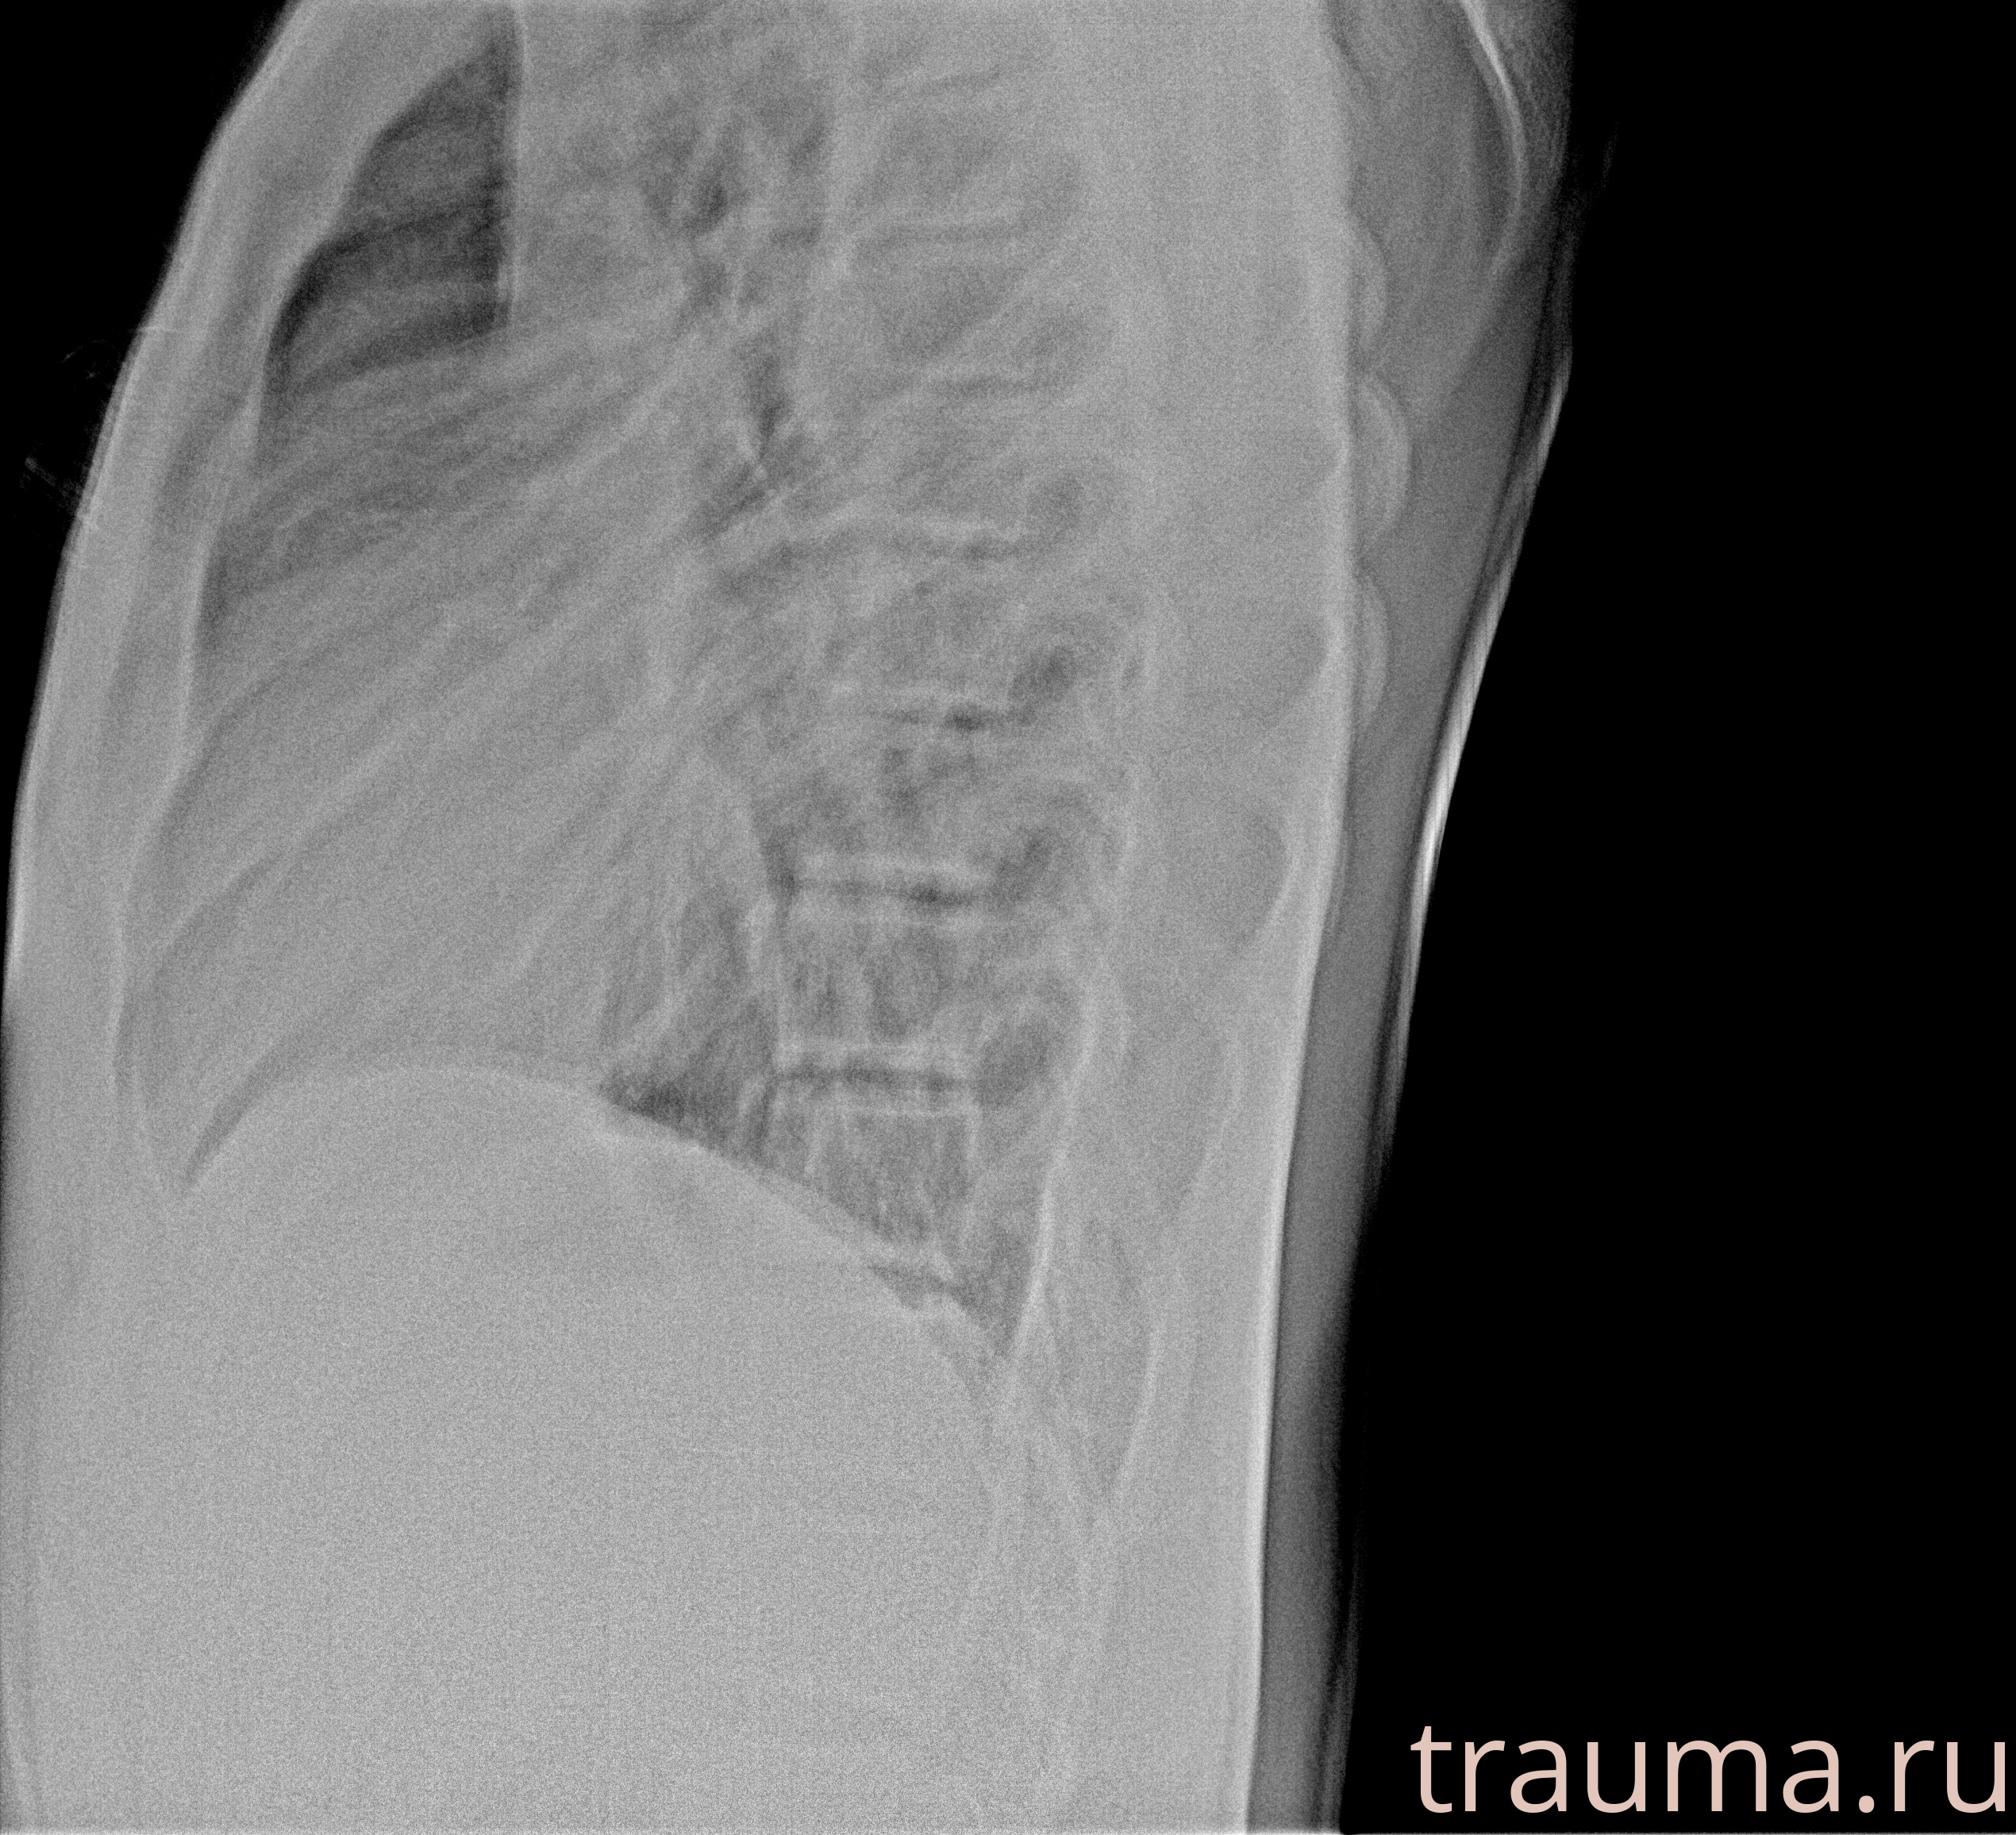

Рентген на дому: по вашему адресу приезжает врач-рентгенолог, травматолог-ортопед с мобильным рентгеновским аппаратом, проводит диагностику травмы или заболевания, делает необходимые рентгенограммы, дает рекомендации по дальнейшему лечению. Получить качественные снимки в домашних условиях возможно благодаря уникальной методике, разработанной МосРентген Центром для института  Склифосовского